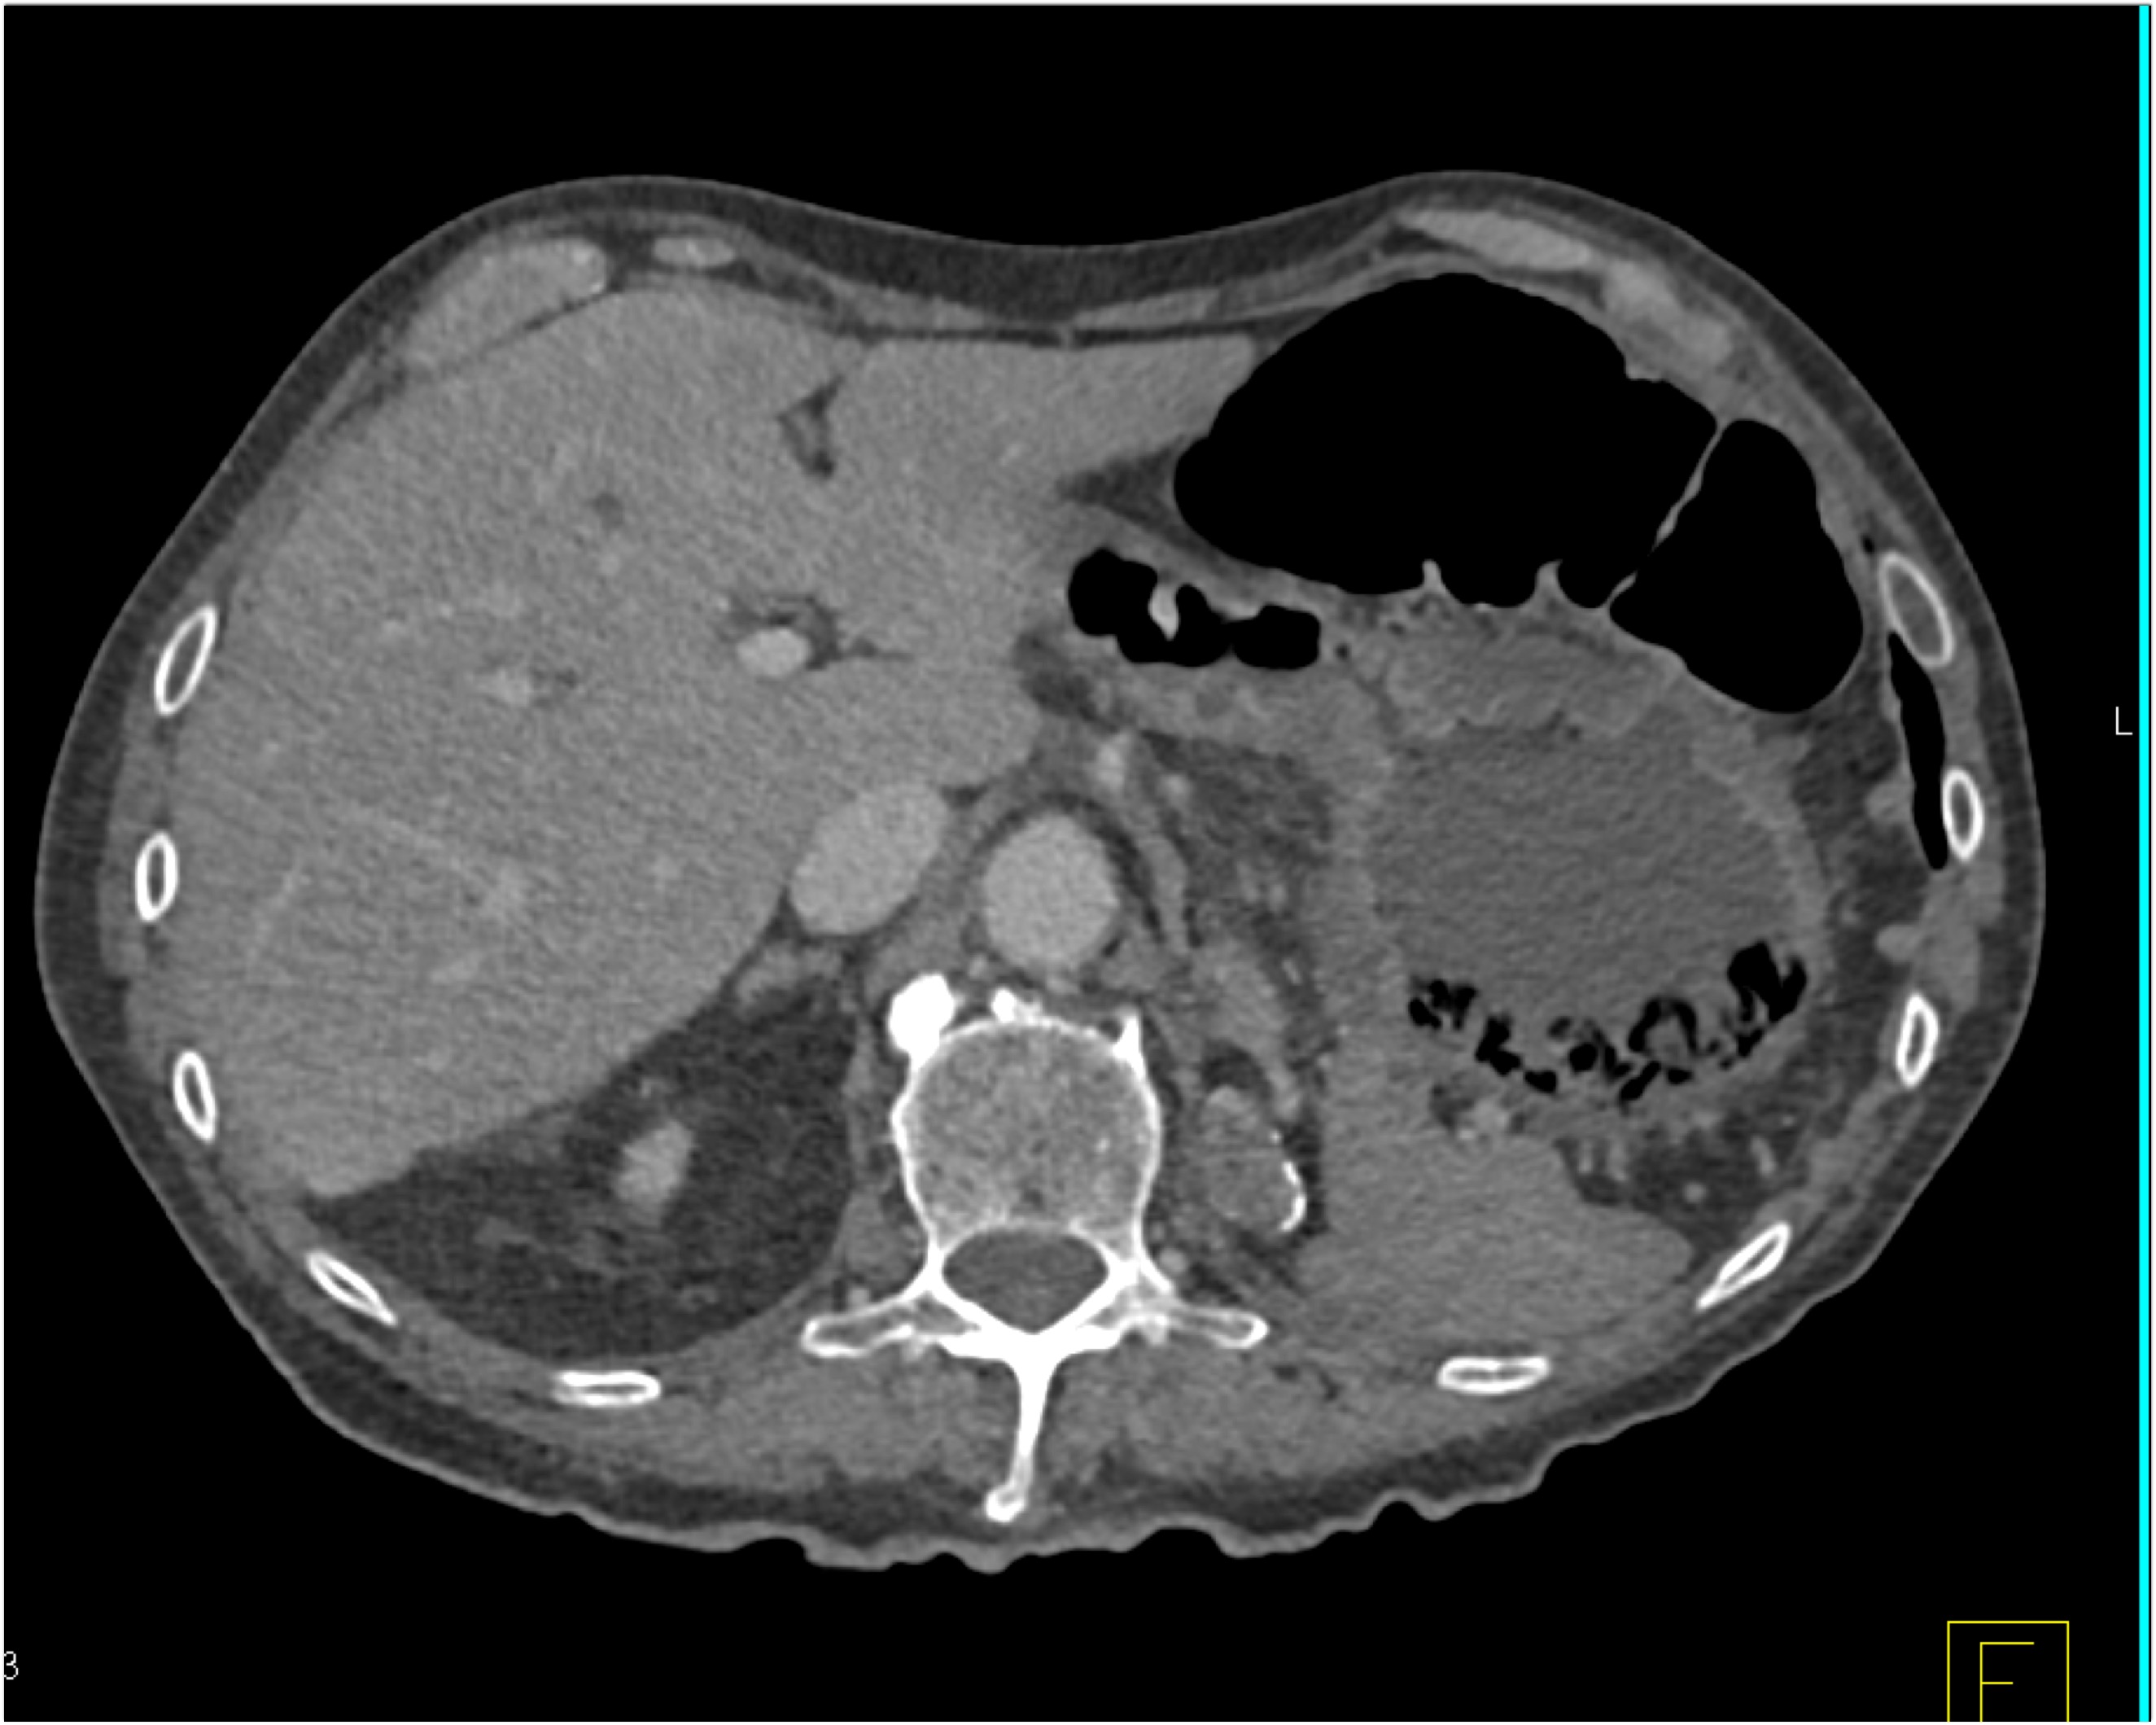

8) In this patient with RUQ pain and no history of trauma the best diagnosis is?

multiple hemangiomas

focal nodular hyperplasia

hepatic adenomas

angiosarcoma of the liver